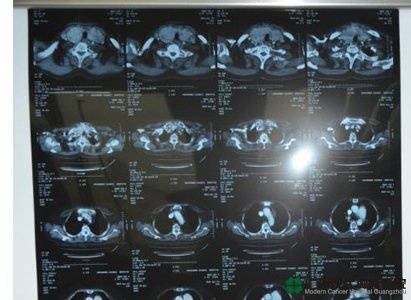

แผ่น CT มะเร็งต่อมน้ำนมของโจวเย่เอ๋อ